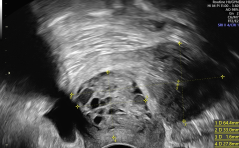

Der suspekte Adnexbefund in der Praxis PDF Dokument

Sonoquiz

Woran denken Sie? PDF Dokument